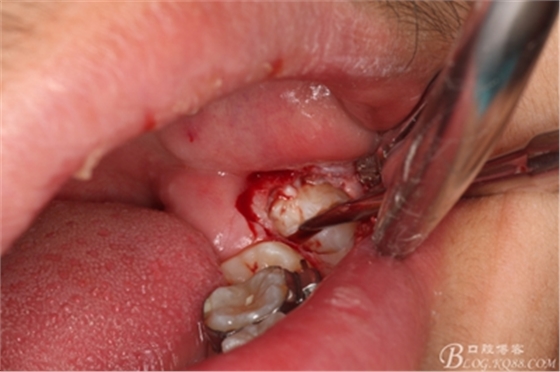

圖9.高速拔牙手機(jī)去骨

圖10.去骨后暴露出38的牙冠

圖11.縱分牙冠